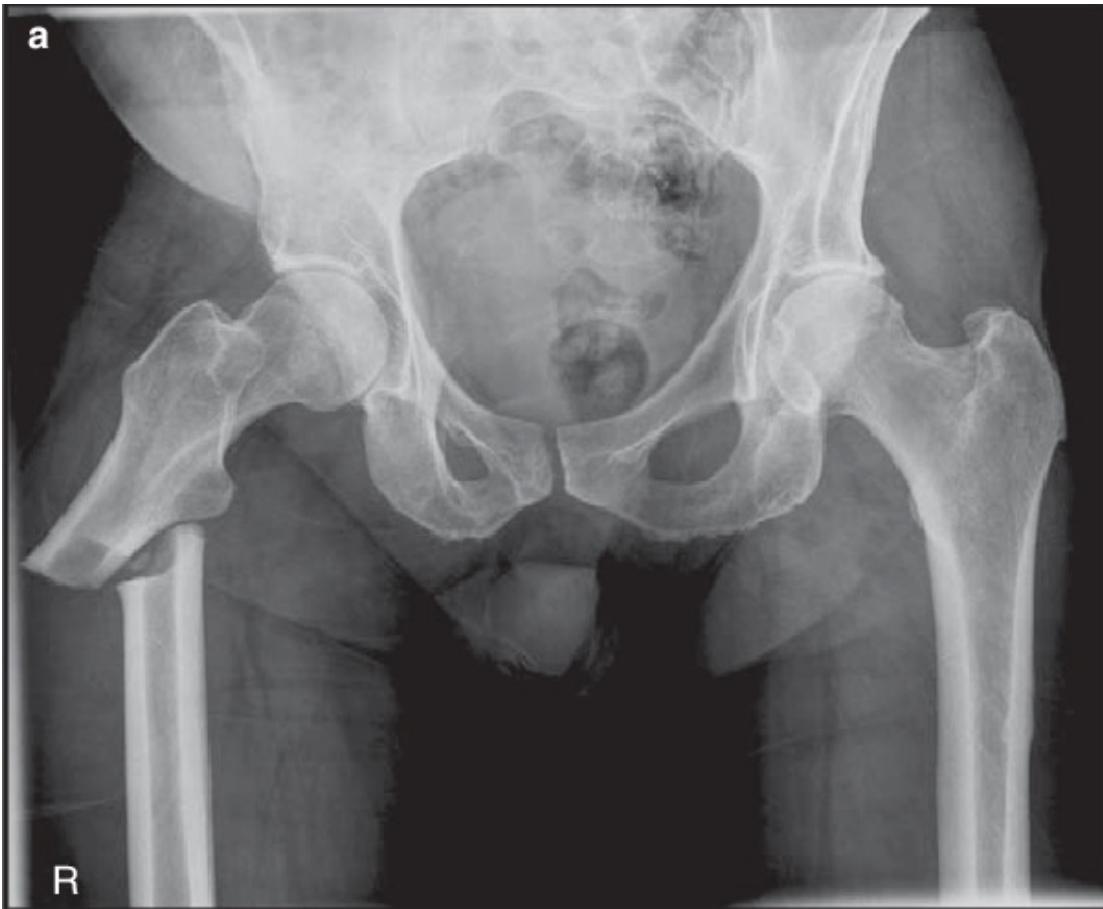

Case B: Pelvic Trauma

4.1) Open Book Fracture Management

1. Diagnosis? Answer: Open book fracture

2. Initial management? Answer: ATLS protocol, pelvic binder application

3. Mention 3 complications: Answer:

- Bleeding

- Pelvic instability

- Neurological injuries

4. Difference between stable and unstable management:

Stable open book fractures can typically be managed non-operatively, with the use of a pelvic binder or external fixation to stabilize the anterior pelvic ring until the injury heals.

Unstable open book fractures require surgical intervention to achieve anatomic reduction and stabilization of both the anterior and posterior pelvic rings.